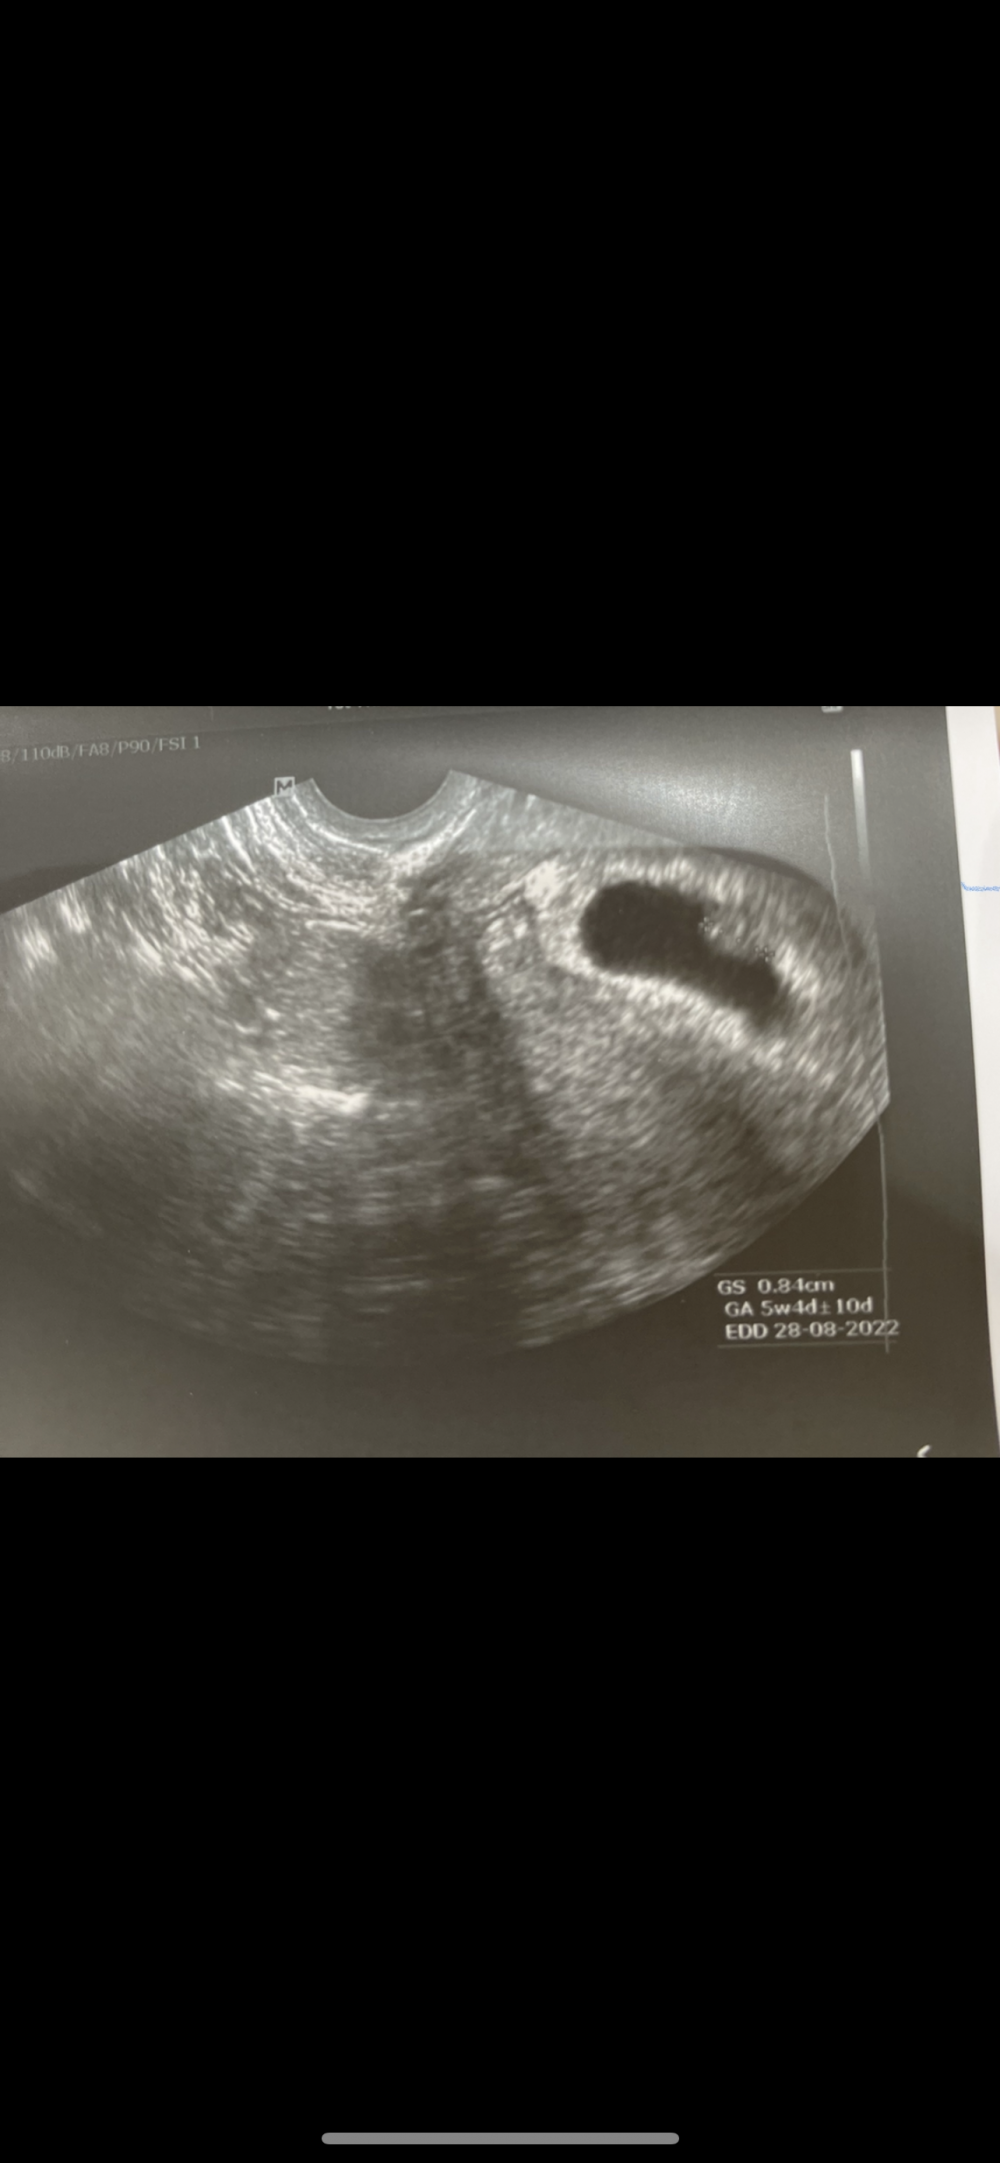

هذا سوناري بالاسبوع السادس مهبلي

حسوا لي واتمنى تحسون لي بنت 🦦